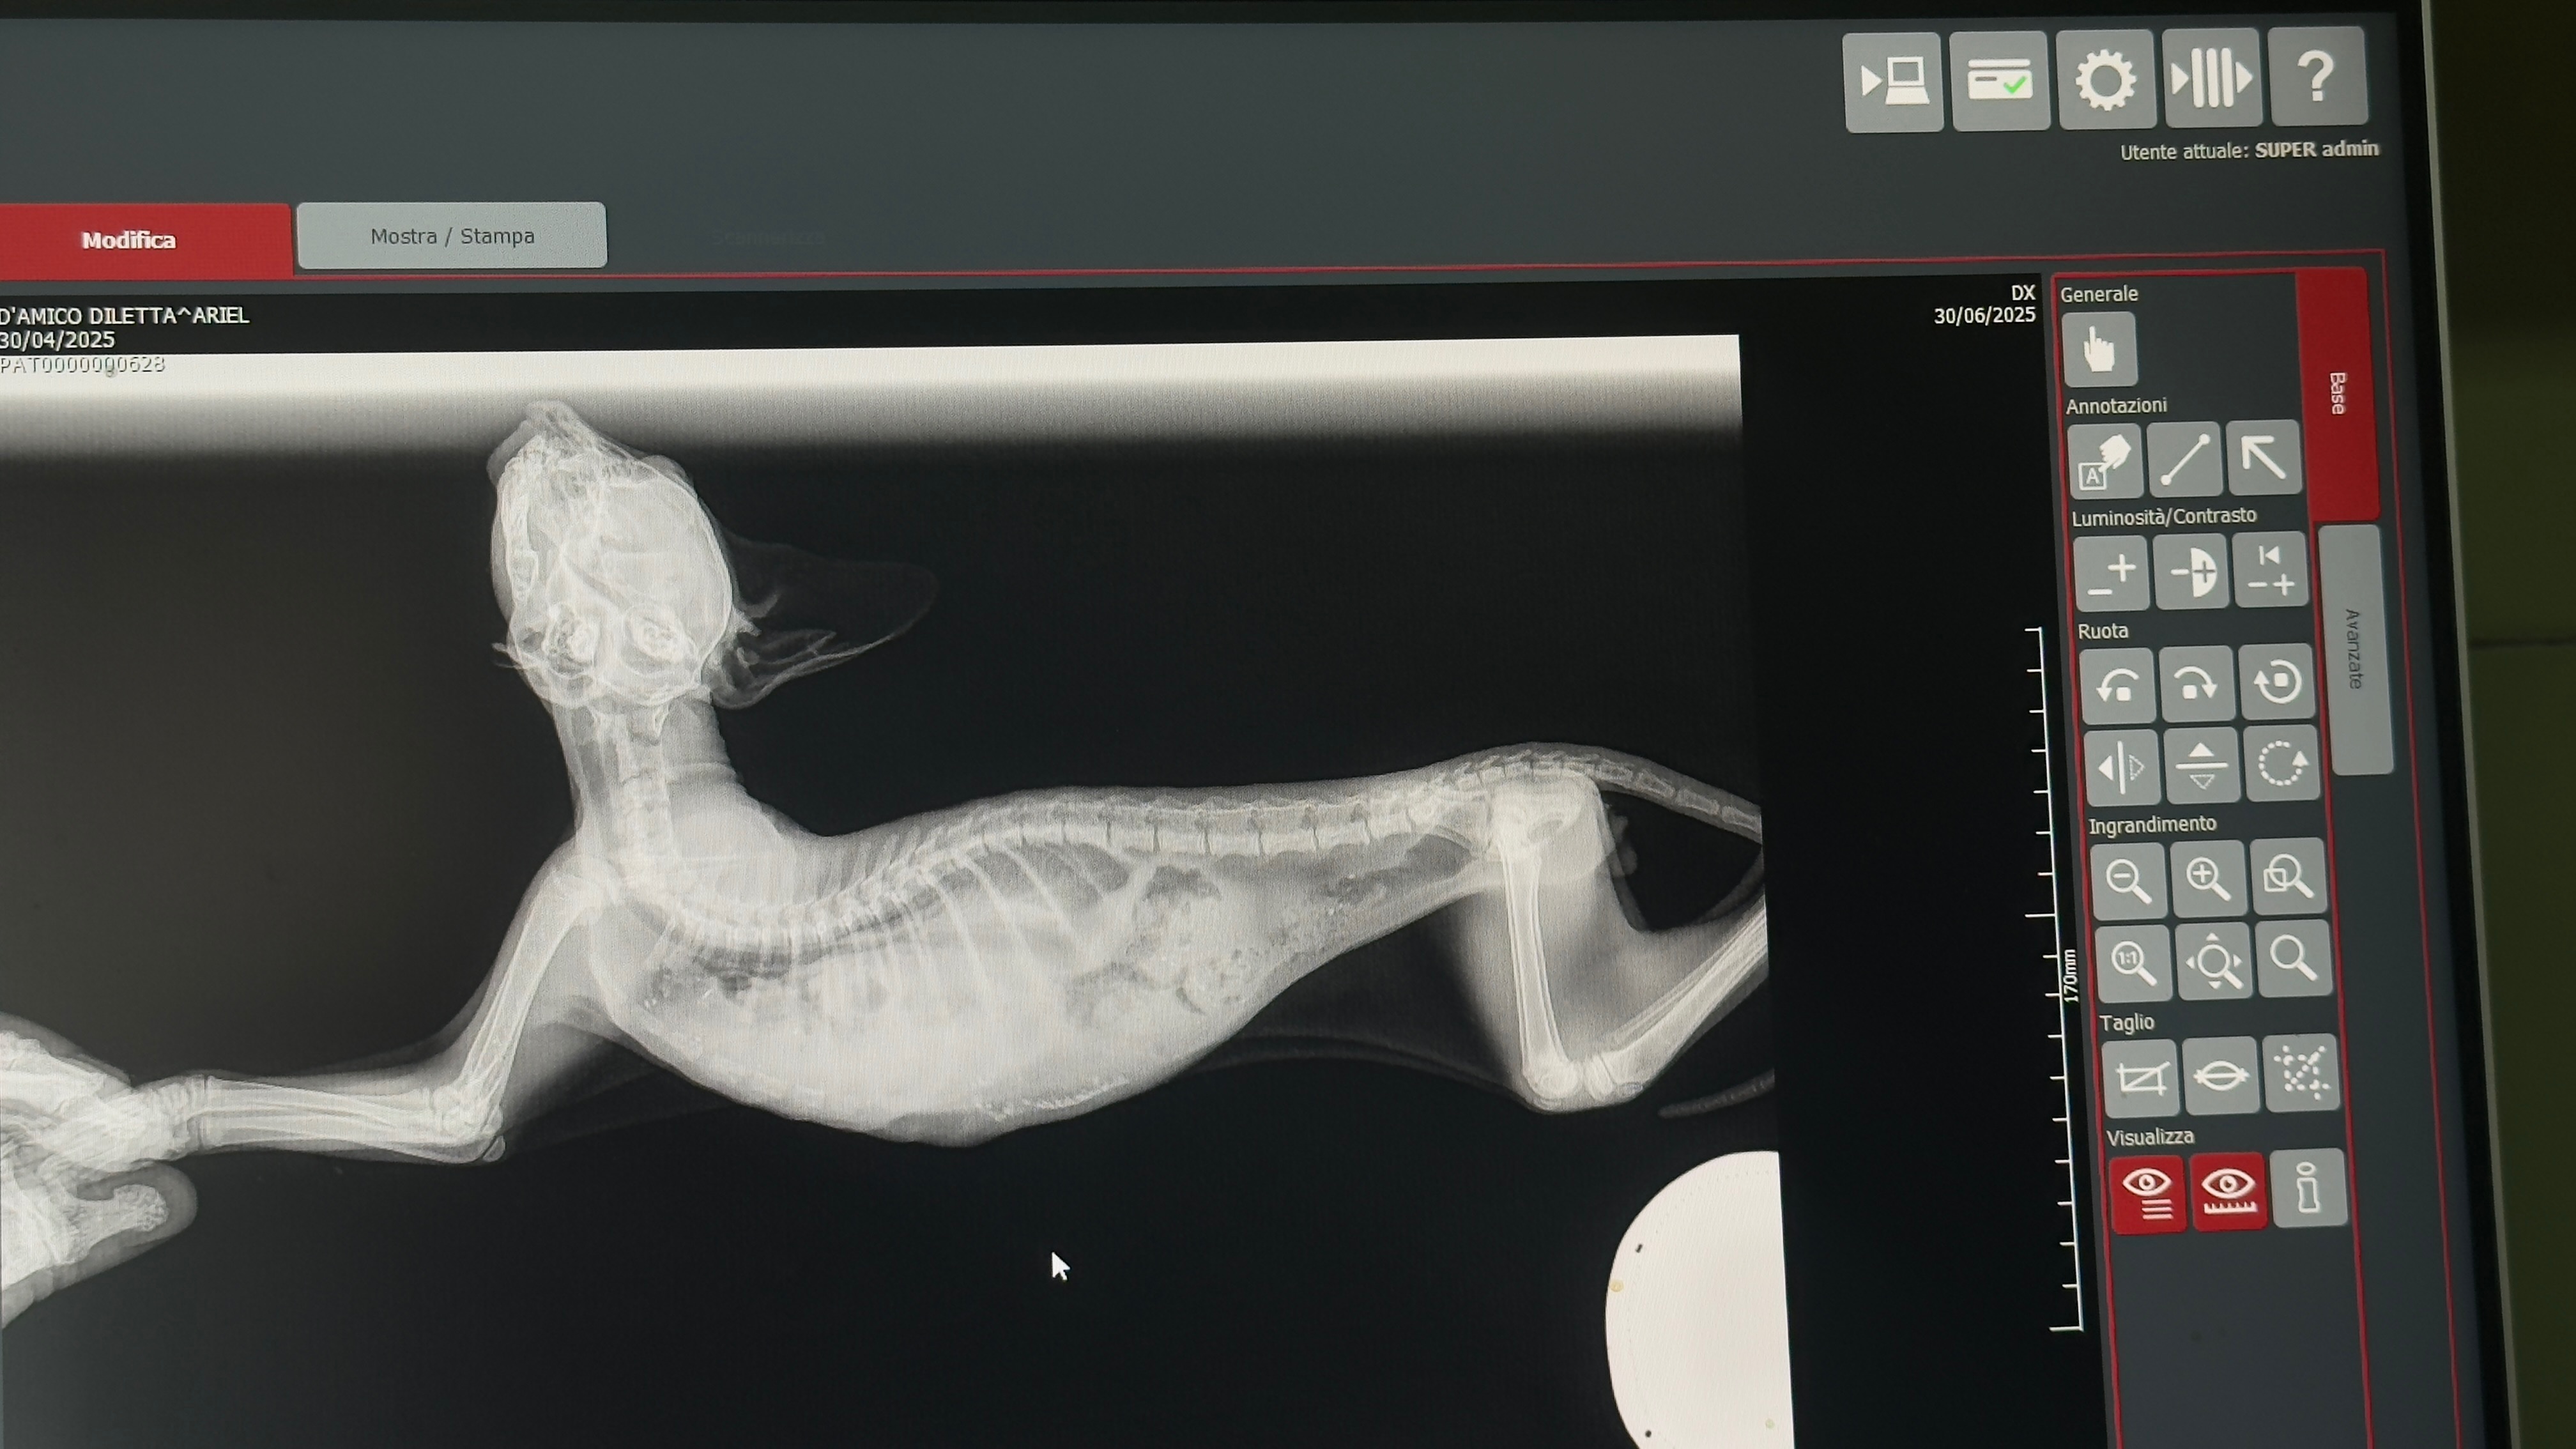

He was breathing slowly and with difficulty… so we took him to the vet. Sadly, we were told he had suffered a severe trauma: in simple terms, his stomach had moved into his chest cavity, putting pressure on his lungs.

The vet confirmed that he urgently needs surgery, which could cost over €500.